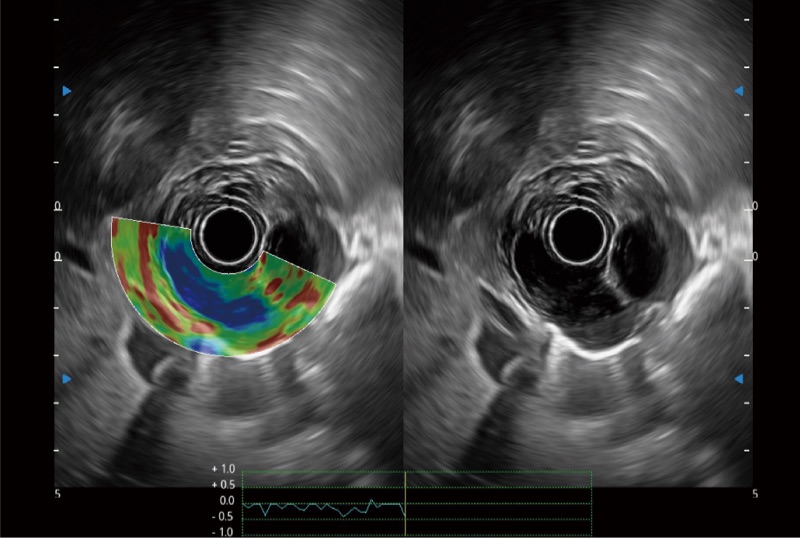

可人为将灰阶图像转变成彩色的显示方式,增强人眼对于不同回声强度的敏感度,主观上增加了图像分辨率

微米成像技术提升了对组织斑点噪声信号的抑制能力,并进一步强化边界信息,从而获得信噪比更优、边界更清楚锐利的图像

随着组织深度的变化,超声接收频率进行智能匹配跟踪,确保图像中、远场良好的穿透力以及整场一致的分辨力,从而得到均一的画质

食管内间质瘤清晰显像

清晰显示胆总管及周围血管分布

肝左叶和肝静脉的横截面